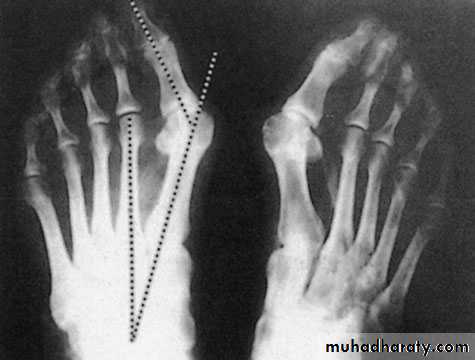

Inter metatarsal angle less than 9 degree &metatarsophal angel angle less than 15 degree

X-ray:

Taken with the patient standing to show the degree of metatarsal and hallux angulations.Also it shows the state of the joint being normal, arthritic or subluxated.

Adolescent congenital deformity always need surgical correction of the varus position of the 1st. metatarsal by osteotomy to put it more straight so the big toe will assume more straight position.For adults:

For those above 40 years with failure of the previous methods we add to the surgery above an osteotomy of the 1st. metatarsal to correct its alignment. There are different types of osteotomies as Basal osteotomy, Mitchell’s osteotomy and Willson’s osteotomy.